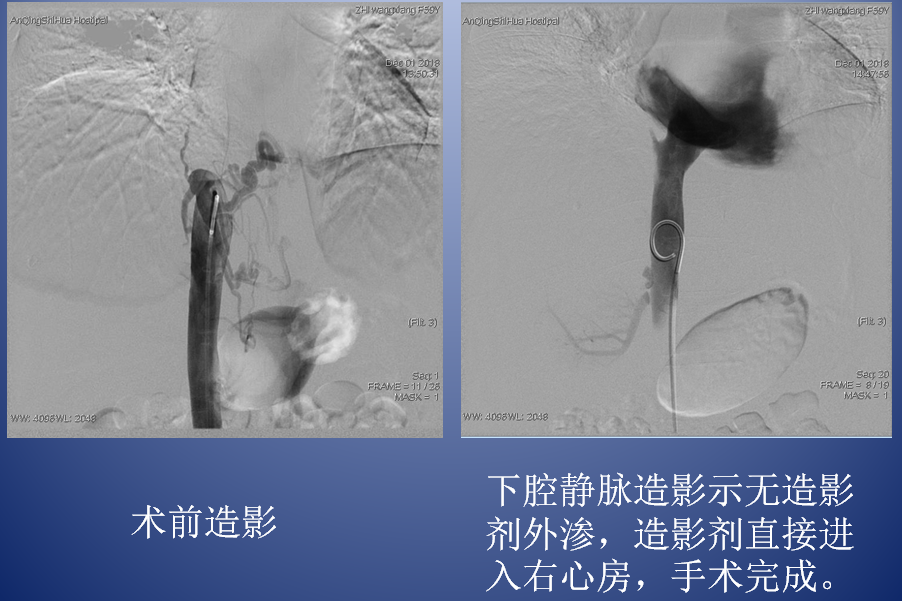

介入治療創(chuàng)傷小、效果好、并發(fā)癥少,是布加氏綜合征的首選治療方式。放射介入科團隊認真分析病因,反復(fù)討論病情,最終為芷女士確定了縝密的手術(shù)治療方案。12月1日,團隊放棄周末休息時間,在外院專家指導(dǎo)下,順利為芷女士實施了腔靜脈開通+球囊擴張術(shù)。術(shù)后,芷女士的下腔靜脈血流立刻恢復(fù)通暢,腹圍漸漸縮小,下肢水腫明顯消退,日前,已康復(fù)出院。